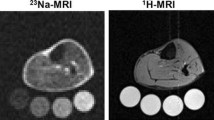

Although it was first suggested by Russian investigators in the 1970s [18], the concept of tissue Na+ was more fully developed by Jens Titze and co-workers over the last 20 years. In keeping with previous evidence of positive Na+ balance without commensurate water retention or body weight increases in subjects on short-term high salt diet [19], they reported a dissociation between Na+ and weight changes in unique long-term (months) observational [20] and interventional [21] studies, thus supporting the idea of a body reservoir for non-osmotic water-free sodium storage. Rat body-composition studies [14, 22–24] and 23Na-magnetic resonance imaging (MRI) in humans [16] pointed to the skin, and to some extent the muscle, as the specific depots for excess Na+ accumulation, with the negatively charged glycosaminoglycans (GAGs) network serving as the dynamically regulated substrate for putative interstitial skin Na+ binding [25].

The long-established association between salt and hypertension made hypertensive rodent models and patients with hypertension the most obvious targets to investigate the biological relevance of the phenomenon. Indeed, salt-sensitive rats exhibited excess skin Na+ retention upon salt-loading, paralleled by water [13, 22] but not to the point of iso-osmotically matching Na+ positive balance [14], and hypertensive patients with refractory hypertension or primary aldosteronism had increased tissue Na+ content compared with normotensive controls [17] or post-adrenalectomy follow-up [16], respectively. From these data, one can draw one first (#1) conclusion: hypertension, particularly, salt-sensitive hypertension, is associated with tissue Na+ accumulation.

An epidemiological association between altered arterial compliance and distensibility with high-salt diet, ultimately resulting in increased vascular resistance, has been suggested long ago [61]. However, more direct evidence in support of the above contentions should refer to tissue, rather than dietary, Na+ and to strategies that are known to reduce its accumulation. While enhancers of the lymphangiogenic response that provides interstitial drainage [23, 24] are still out of sight, different classes of natriuretic agents have consistently shown potential in this regard. Mineralocorticoid receptor antagonists (MRA) [16, 62•], loop diuretics [63], as well as the novel sodium-glucose co-transporter-2 (SGLT2) inhibitors [64] were all shown to reduce tissue Na+ content by means of 23Na-MRI.

The remarkable expansion of 23Na-MRI data in the last few years has made very clear that, in addition to patient with hypertension, excess tissue Na+ signal is prevalent in a multitude of traditional cardiovascular risk factors and conditions, including heart failure [63] and chronic kidney disease [29]. After the first reports [64], patients with type-2 diabetes were recently shown to accumulate even greater skin and muscle Na+ than patients with primary hypertension [83•].